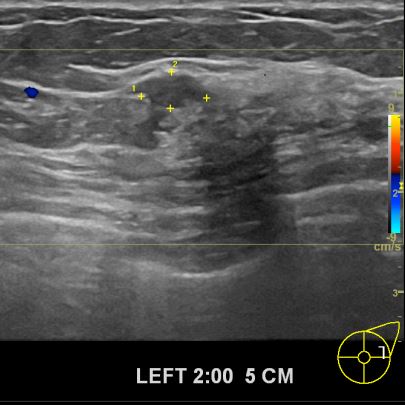

외부검사상 이상소견으로 조직검사권유 받아  내원하신 50대 여성분으로

좌측유방 조직검사 시행후 유방암 진단되었읍니다.빠른 쾌유바랍니다.